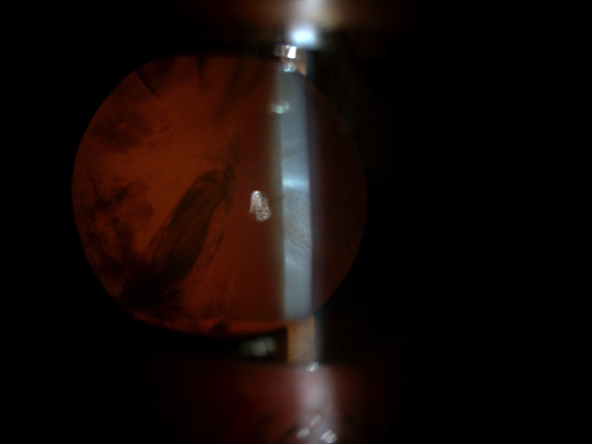

El cristalino es como una lenteja, transparente, que colabora en el enfoque de la imagen sobre la retina. La catarata consiste en la opacificación de esta “lenteja”. En la actualidad, el único tratamiento disponible para la catarata es la cirugía. Antiguamente, las técnicas intracapsulares obligaban a realizar una incisión amplia, comprendiendo casi los 180º superiores, se extraía todo el cristalino y, o bien se corregía la graduación en gafa, o bien se implantaba una lente de apoyo angular en cámara anterior (cuando estas estuvieron disponibles).

Cuando se dispuso de lentes de cámara posterior, se recuperó el interés por las técnicas extracapsulares, donde se extrae la catarata a través de una apertura en la capsula anterior del cristalino, pero dejando el resto. Es decir, volviendo al “símil de la lenteja”, se retira el contenido de la misma, pero dejando la piel, lo que será el saco donde se implantará la lente intraocular artificial que hará las veces del cristalino antes de opacificarse. Esta técnica también requería de una incisión generosa (6-7mm) y suturas que habitualmente causaban astigmatismo durante el postoperatorio.

Actualmente, el estándar para la cirugía de catarata es la facoemulsificación, lo que permite extraer la catarata a través de incisiones de 2 a 3mm. Con un sistema de ultrasonidos la catarata se deshace y se aspira, tras lo que se implanta la lente que restaurará la visión, siendo este sistema menos agresivo que las técnicas previas y el postoperatorio mucho más rápido. Así, hoy ya no se espera a que la catarata “este madura”, ya que las exigencias laborales del mundo actual y dada la seguridad de la técnica, hace razonable intervenir la catarata cuando al paciente le limita su vida normal (laboral, ocio, etc). Incluso en pacientes de mayor edad se ha estudiado2,3 que, tras operar un solo ojo, habiendo catarata en ambos, el riesgo de caídas y fracturas asociadas disminuye significativamente.

Alguna de las circunstancias que pueden hacer la cirugía más laboriosa es la insuficiente dilatación de la pupila o el cierre de la misma durante la intervención, más frecuente en pacientes que toman tratamientos para la hiperplasia benigna de próstata, que con frecuencia afectan al iris, causando lo que se denomina Sindrome de Iris Flacido. En el siguiente video, podemos ver el ejemplo del segundo ojo de un caso así, donde directamente, por la experiencia vivida en el otro ojo, dilatamos la pupila mecánicamente con retractores de iris en previsión de posibles complicaciones, completando la cirugía sin incidencias.

Otras circunstancias, como la debilidad zonular, pueden dificultar la cirugía, e incluso si esta es muy acusada llegar a imposibilitar el implante de la lente en el saco capsular y precisar de una segunda intervención para implantarla. En el último video, se ve como la catarata presenta una debilidad zonular, detectada intraoperatoriamente, que puede ser manejada con los mismos ganchos de iris manteniendo la capsula “in situ” y tensándola al final de la cirugía con un anillo de tensión capsular.